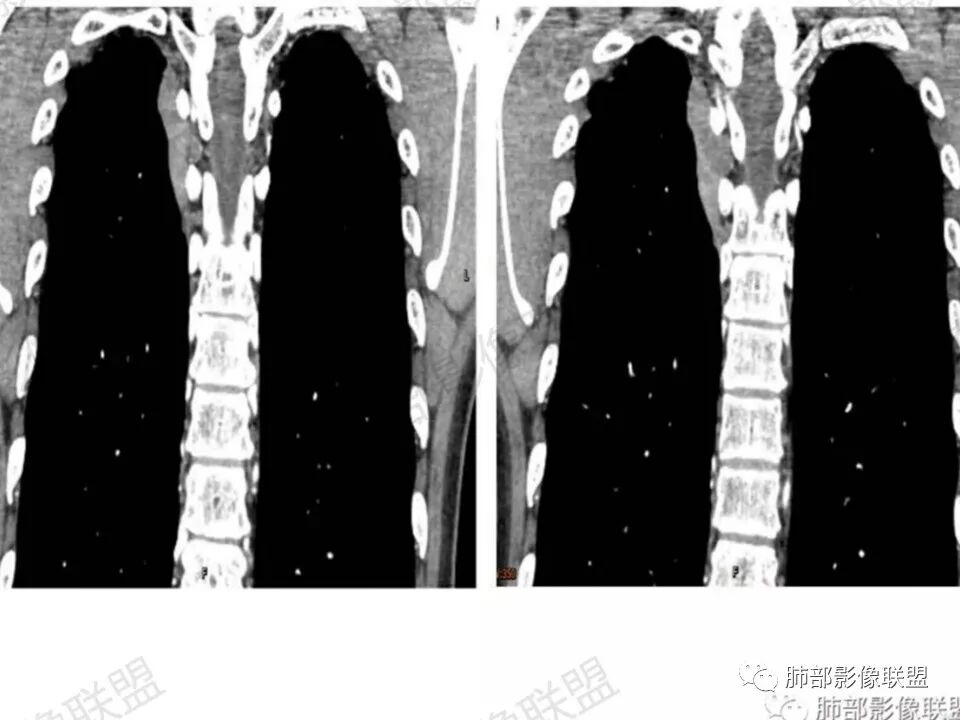

男,45岁,反复背痛3年;病程长,发展缓慢;后纵膈,与脊柱关系说不清;强化明显,有分区;诊断:神经源肿瘤;良性鉴别:间质来源肿瘤。

这个病例定位肺外没问题,病灶呈宽基底,见明显的胸膜掀起征,定位胸膜或右后纵隔来源,而且肿块提示肋间动脉穿行,脏层胸膜来源可能性不大(脏层胸膜由肺动脉及支气管动脉供血),那就是壁层胸膜跟纵隔来源,但是图像上有2个层面是胸膜外间隙有受压推移,所以壁层胸膜来源也不考虑;病灶是渐进性强化,常见的就是间叶来源含有梭形细胞的软组织肿瘤跟后纵隔常见的神经源性肿瘤鉴别,那如何在后纵隔的大山里拨开云雾找到我们想要的答案呢?那小编在这里先理出几个问题:

答:神经源性肿瘤的解剖位置及形态很重要—沿神经干方向生长走行。后纵膈内神经鞘瘤最常见的是神经根出入椎间孔处,并可沿着肋间神经方向分布,所以后纵膈神经鞘瘤通常横径大,上下径小,这个病例明显上下径长,所以不符合神经鞘瘤;神经节细胞瘤可沿着椎旁上下方向分布(参见上图黄色梭形的神经节),所以表现为上下径长,虽然生长方式符合,但是节细胞瘤以粘液为主,易钙化,该病例成分及强化方式不符合。